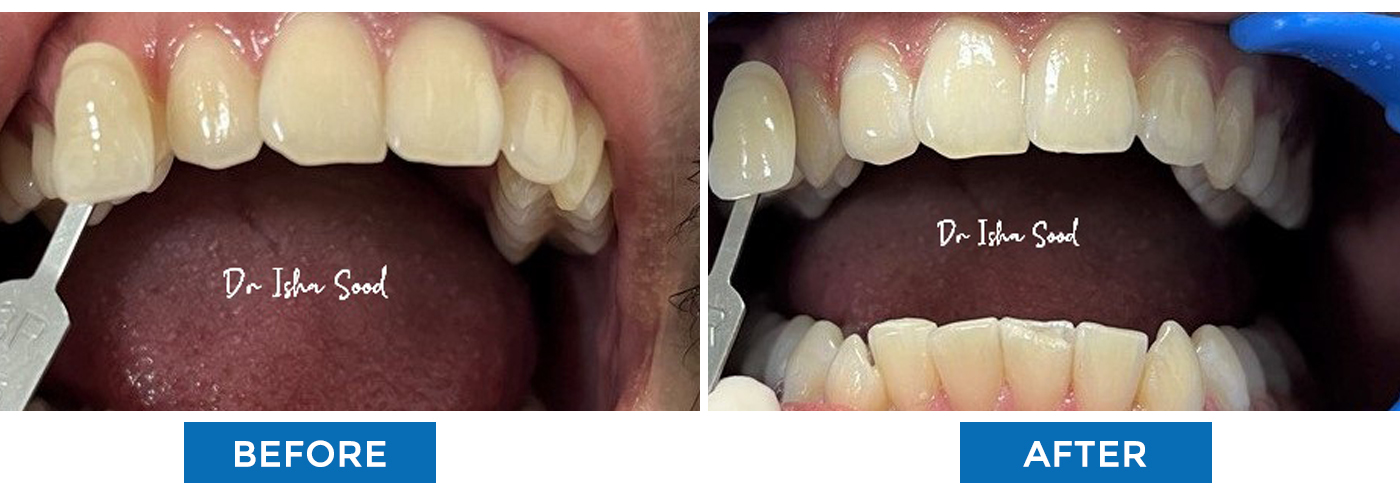

Broken Tooth Repaired with Tooth Coloured Filling

Discoloured Fillings Changed to Tooth Coloured

Aesthetic Filling